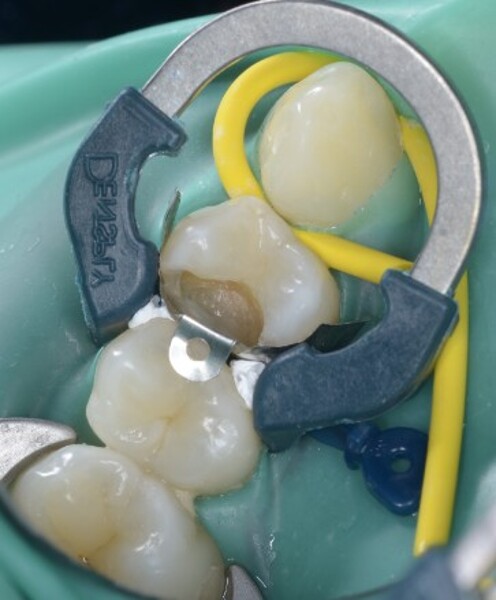

Predictable posterior restorations